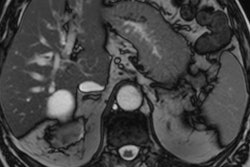

Prof. Okan Akhan from Ankara. Courtesy of BIR.The 33-minute discussion focuses on percutaneous biopsy and why certain patients may benefit from this treatment, common potential postoperative complications and how these can be managed, and palliative care using IR. It also covers treatment options for patients with locally advanced pancreatic adenocarcinoma as well as patients with metastatic disease.

"Interventional radiology provides a wide range of safe and effective treatment modalities for pancreatic cancer patients in every step of the disease, starting from initial diagnosis to the end," Akhan said. "Despite the poor prognosis and high mortality of the disease, IR provides highly effective, minimally invasive solutions for pancreatic cancer patients to improve their quality of life."